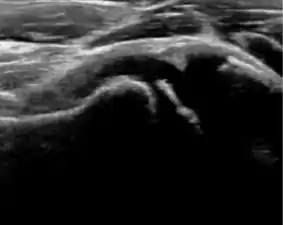

Ultrasound

Ultrasound is the first-choice technique for diagnosis of newborns hip dysplasia. In experienced hands with appropriate technology, ultrasound can also be useful during the first year of life. Some European healthcare systems encourage universal ultrasound screening in neonates between the sixth and eighth weeks. Although it shows higher initial costs caused, it leads to significant reduction in the total number and overall costs of dysplastic hips undergoing operative and nonoperative treatment.[1]

Ultrasound allows categorizing pediatric hips, according to Graf’s criteria, in four main types: normal, immature, and dysplastic (subluxed and dislocated). This classification is based on measurements of the acetabular inclination angle (alpha), cartilage roof angle (beta), and infant age. The femoral head coverage can also be determined by dividing the length of the femoral head covered by the acetabular fossa and the diameter of the femoral head. Its lower normal limits are 47% for boys and 44% for girls (Figure 11).[1]

During childhood, ultrasound is a quick method to assess hip pain and quite often may be used to avoid use of irradiating techniques, such as radiography or CT. Ultrasound allows evaluation of joint effusion, synovial thickening and neovascularity, the bone/cartilage contour, and the femoral head-neck alignment. Although sonography is extremely sensitive in detecting increased synovial fluid, it is nonspecific and cannot be used with accuracy to determine the type of fluid. Transient synovitis of the hip, despite being the most frequent cause of pain in children between 3 and 10 years, remains a diagnosis of exclusion. It usually shows anechoic fluid, but echogenic fluid can also be found. The effusion is considered pathologic when it is measured at >2 mm in thickness. The differential diagnosis is wide, including osteomyelitis, septic arthritis, primary or metastatic lesions, LCPD, and SCFE. Discrimination from septic arthritis is challenging, often requiring joint aspiration. In septic arthritis, US is able to demonstrate a hip joint effusion, synovial thickening, and cartilage damage, although the appearances are nonspecific.[1]

Figure 12:

Normal ultrasound appearance of the femoral head-neck junction.

Joint effusion in transient synovitis of the hip.

Flattening of the femoral head in a patient with Perthes disease.

Step in the femoral head-neck junction in a patient with SCFE.